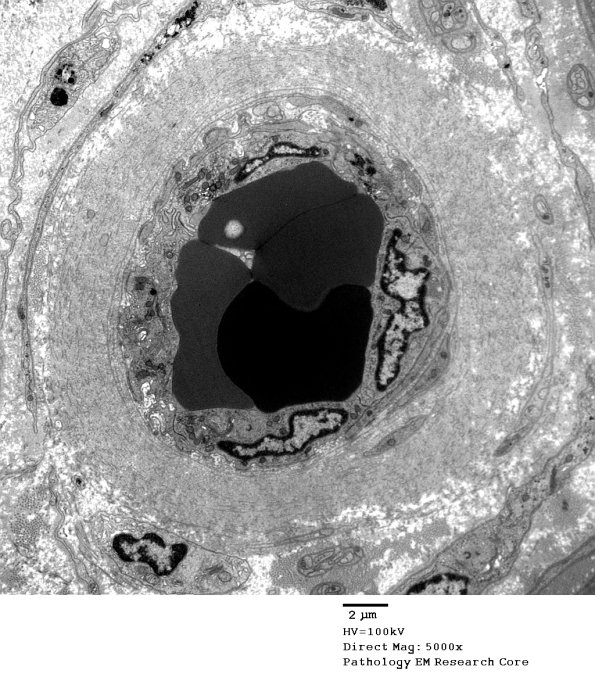

Washington University Experience | VASCULAR | Hypoxia-Ischemia, fetal-neonatal | White Matter | 2D1A Vasculopathy (Case 2) EM 008 - Copy

2D1A Vasculopathy (Case 2) EM 008 - Copy